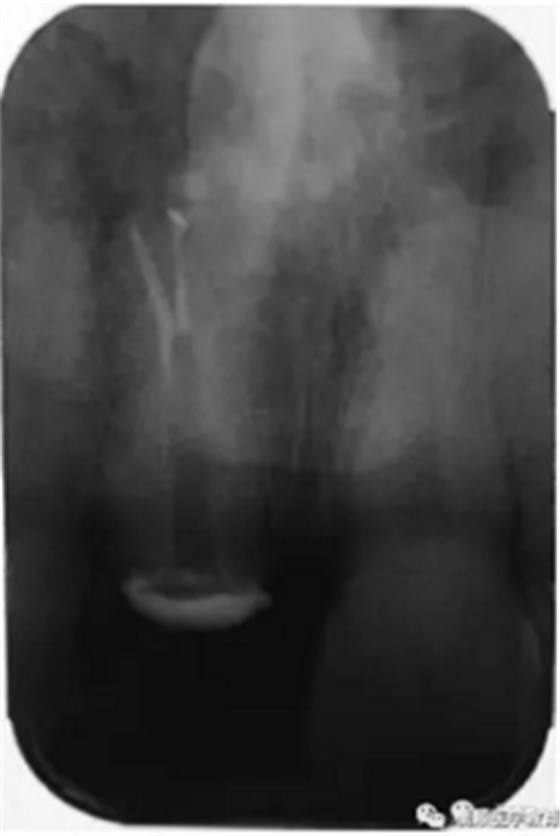

基于臨床檢查和X線(xiàn)片顯示,診斷為右上頜中切牙根尖周炎伴額外牙。治療計(jì)劃是先行患牙的根管治療,制作臨時(shí)義齒,最后制作樁核冠。應(yīng)用橡皮樟和顯微根管技術(shù),利用ProTaper旋轉(zhuǎn)銼配合使用 Hedstrom 銼和桉葉油,將根管內(nèi)充填物取出,觀(guān)察X線(xiàn)片可見(jiàn)根尖三分之一處主根管一分為二,確定另一根管的工作長(zhǎng)度,兩根管同行常規(guī)根管治療,充填后X線(xiàn)片顯示根管充填良好。樁核冠修復(fù)1年后,患牙無(wú)疼痛,影像檢查發(fā)現(xiàn)根尖顯影正常,根尖疾病治愈。

圖2. 患牙根管充填后即刻X線(xiàn)片顯影